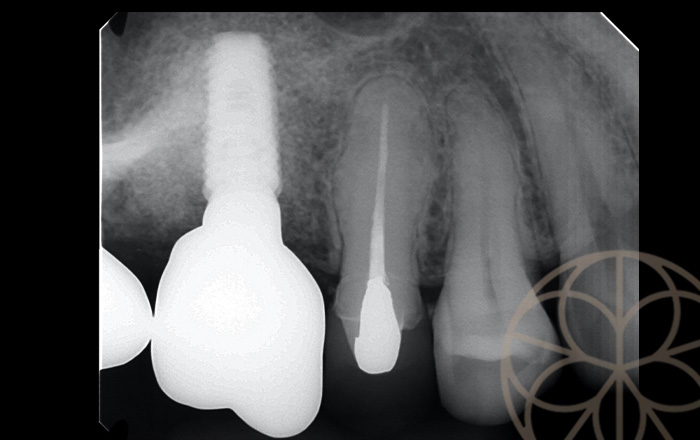

治療前状況①

インプラント

治療前状況②

根の部分で破折しており、残念ながら、

どのような方法をとっても歯を残せる状態ではないと診断しました。

この歯が悪くなってしまった理由として、咬み合わせが悪く、特定の歯のみねじれるような力がかかるという可能性があります。今回破折していた、銀歯の一つ前のセラミックも強くあたっているため、セラミックの一部がかけており、強く負担がかかっていることが示唆されます。